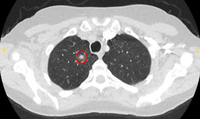

Computed tomography (CT) sections with examples of semi-solid solitary nodules

From the collection of Dr George Tsaknis, MD, PhD, FRCP(London), MRQA, MAcadMEd, PGCert; used with permission